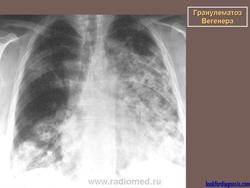

Поражение легкихразвивается у 3/4 больных, проявляется формированием инфильтратов, которые могут распадаться и образовывать полости. Иногда наблюдается плеврит.

При генерализованной форме ........ картина пневмонии с наклонностью к абсцедированию и появлению плеврального выпота.

Рентгенологическое исследование легких: инфильтраты, часто с распадом и образованием полостей, редко - плеврит.